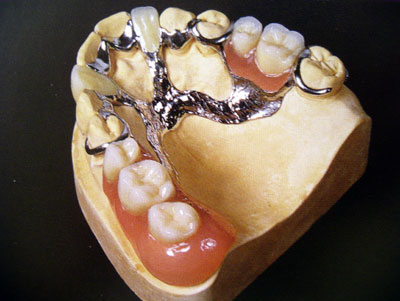

Ортопедия →Бюгельное протезирование

Бюгельный протез - это вид съемного протеза позволяющий использовать для опоры помимо десны и собственные зубы. Протез во рту занимает меньше объема, становится значительно прочнее, долговечнее, удобнее. Немаловажно, что способ передачи жевательной нагрузки в данном случае ближе к физиологическому, по сравнению с пластиночными съёмными протезами.  Различают бюгельные протезы с кламмерами и бюгельные протезы с замками. В первом случае удержание протеза на зубах осуществляется с помощью особых крючков, которые плотно охватывая зуб, не причиняя вреда эмали, удерживают протез. Во втором случае крепление протеза очень жёсткое, протез неподвижен и снимется только открыв замок Большая часть жевательного давления перераспределяется на опорные зубы, на которые надеты специальные металлокерамические коронки. Замки скрыты внутри протеза и незаметны.